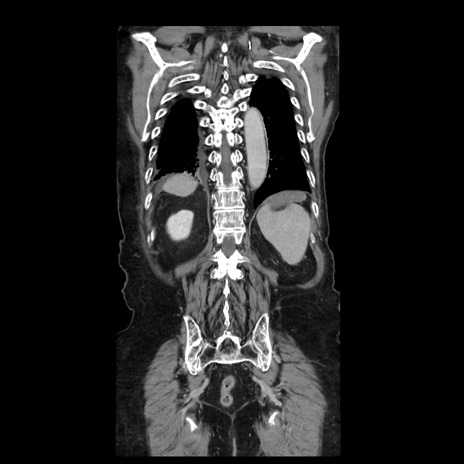

横断像

【症例】70歳代男性

【主訴】腹痛

【現病歴】肝硬変・肝細胞癌にてかかりつけの方。約9時間前に食後より腹痛出現。症状が徐々に増悪し、嘔吐出現したため来院。

【既往歴】肝硬変、肝細胞癌(RFA、TACE後)

【身体所見】意識清明、表情苦悶様、BT 36℃、BP 129/78mmHg、P 88bpm、SpO2 97%(RA)、右上腹部から心窩部にかけて圧痛あり、反跳痛なし、筋性防御あり。

【データ】WBC 5800、CRP 0.16